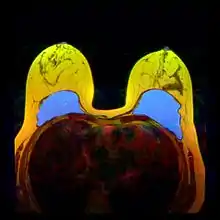

The human body's immune response to a surgically installed foreign object—breast implant, cardiac pacemaker, orthopedic prosthesis—is to encapsulate it with scar tissue capsules of tightly woven collagen fibers, in order to maintain the integrity of the body by isolating the foreign object, and so tolerate its presence. Capsular contracture—which should be distinguished from normal capsular tissue—occurs when the collagen-fiber capsule thickens and compresses the breast implant; it is a painful complication that might distort either the breast implant, or the breast, or both. Capsular contracture is diagnosed through a visual and physical examiniation according to level of increasing severity based on the Baker Grade scale: Baker Grade I, Baker Grade II, Baker Grade III, and Baker Grade IV.

The cause of capsular contracture is unknown, but the common incidence factors include bacterial contamination, device-shell rupture, filler leakage, and hematoma. The surgical implantation procedures that have reduced the incidence of capsular contracture include submuscular emplacement, the use of breast implants with a textured surface (polyurethane-coated);[61][62][63] limited pre-operative handling of the implants, limited contact with the chest skin of the implant pocket before the emplacement of the breast implant, and irrigation of the recipient site with triple-antibiotic solutions.[64][65]

The correction of capsular contracture might require an open capsulotomy (surgical release) of the collagen-fiber capsule, or the removal, and possible replacement, of the breast implant. Furthermore, in treating capsular contracture, the closed capsulotomy (disruption via external manipulation) once was a common maneuver for treating hard capsules, but now is a discouraged technique, because it can rupture the breast implant. Non-surgical treatments for collagen-fiber capsules include massage, external ultrasonic therapy, leukotriene pathway inhibitors such as zafirlukast (Accolate) or montelukast (Singulair), and pulsed electromagnetic field therapy (PEMFT).[66][67][68][69]